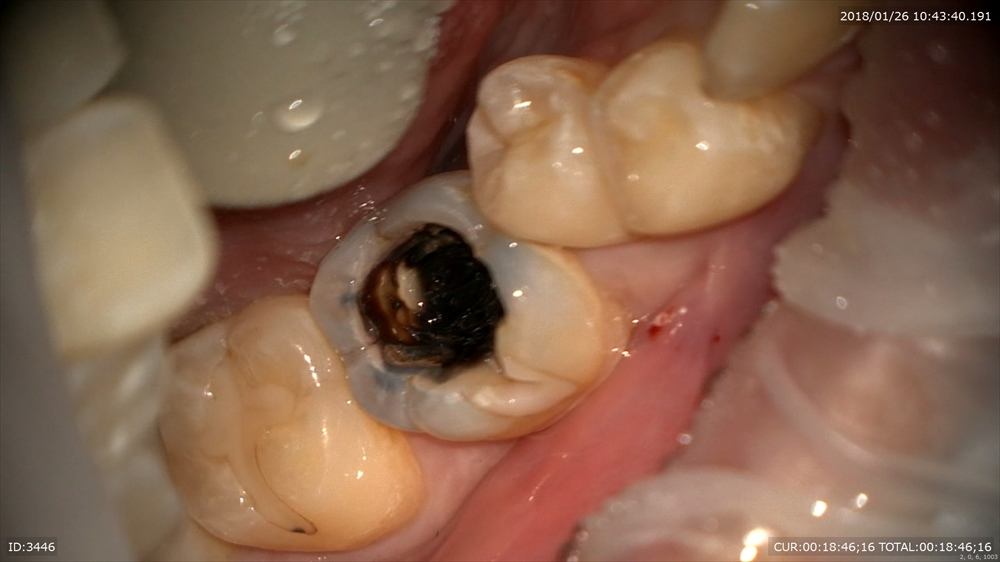

神経に近い所はMTAセメントで

二層目

マイクロスコープで直視できます。ピコモラー最高!!